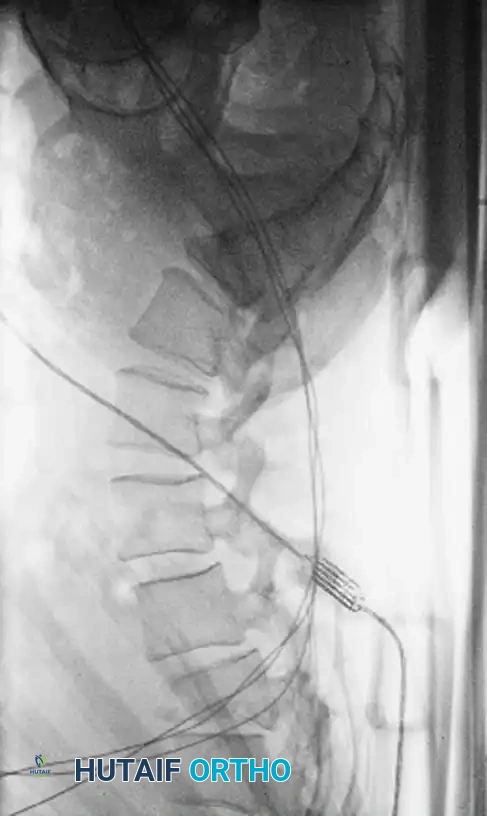

Associated Surgical & Radiographic Imaging